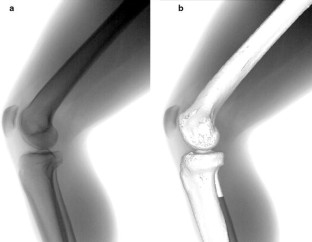

Dynamic motion of the right knee was analyzed in 20 healthy volunteers (10 female, 10 male; mean age 37.2 years). Knee motion was observed as subjects squatted from standing with knee fully extended to maximum flexion. The following parameters were determined: (1) Anteroposterior translations of the medial and lateral ends of the TEA; and (2) changes in the angle of the TEA on the tibial axial plane (rotation angle).

The medial end of the TEA demonstrated anterior translation (3.6 ± 3.0 mm) from full extension to 30° flexion and demonstrated posterior translation (18.1 ± 3.7 mm) after 30°, while the lateral end of the TEA demonstrated consistent posterior translation (31.1 ± 7.3 mm) throughout knee flexion. All subjects exhibited femoral external rotation (16.9 ± 6.2°) relative to the tibia throughout knee flexion.